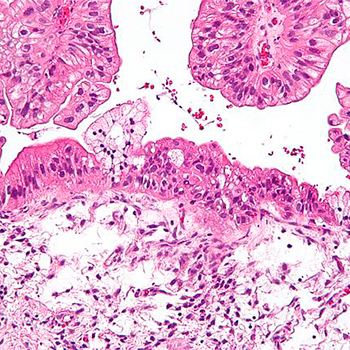

Nueva diana terapéutica para combatir la metástasis en cáncer de ovario

Científicos del <a href="https://idibell.cat/es/" title="Instituto de Investigación Biomédica de Bellvitge" alt="Instituto de Investigación Biomédica de Bellvitge" target="_blank">Instituto de Investigación Biomédica de Bellvitge</a> (IDIBELL) han identificado un receptor celular clave en los procesos de metástasis en cáncer de ovario que podría usarse como diana terapéutica en las variantes más agresivas de la enfermedad.